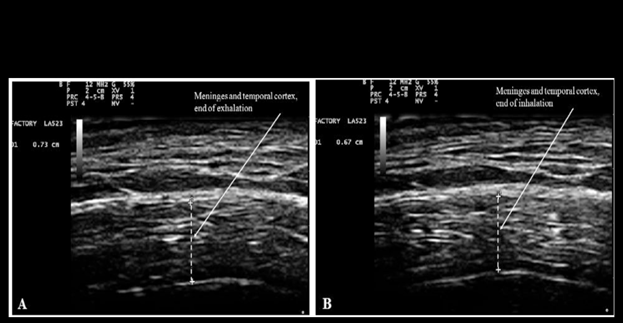

Since the chanting of Nam-Myoho-Renge-Kyo is characterized by a peculiar pattern of respiration with rapid inspiration and prolonged exhalation, the effects of breathing on brain movements are here reported. Morphology of brain structures was previously studied by the author and his colleagues using transcranial ultrasonography as described in Ruggiero et al.12s Bradstreet et al.13 and Ruggiero.14 Briefly, transcranial ultrasonography of the temporal lobe of the brain was performed using an Esaote MyLabFive (Esaote, SpA, Firenze, Italy) ultrasound system with a linear probe for muscle-skeletal examination (LA 523 by Esaote). The settings were adjusted for adult transcranial imaging as described in Ruggiero et al.12 The probe was positioned onto the temporal region of the head corresponding to the squama of the temporal bone, gently tilting it until the hyper-echoic line corresponding to the squama of the temporal bone was horizontal. The results depicted in Figure 1 were obtained at the Department of Human Anatomy, Histology and Forensic Medicine of the University of Firenze, Italy. These images are here reported, and their significance discussed, in the context of the object of this article. Figure 1 below is reproduced from Ruggiero et al.12 under the terms allowed by Firenze University Press. The rationale for investigating brain movements stems from the observation that breathing-induced alterations in brain water content influence sound wave propagation. Since the speed of sound propagation is directly related to the medium's water content, these transient changes in brain hydration modulate the transmission of sound waves within the brain.

The author's brain activity in the Brodmann area 10 of the prefrontal cortex increased by 11% during the 5 min neurofeedback training session performed before chanting. Such an increase is typical for non-trained subjects. In the session performed during chanting, however, the increase of brain activity in the prefrontal cortex was very modest (3%). Conversely, a large increase (52%) of brain activity in the prefrontal cortex was recorded in the session performed immediately after chanting. The results concerning the increase following chanting are consistent with previous studies demonstrating that meditation enhances blood flow in the prefrontal cortex.26,27 The results concerning the relative decrease observed during chanting are consistent with the fact that chanting induces a state of focused attention that leads to a decrease of blood flow to brain regions associated with mind wandering or external stimuli processing. Chanting might induce a shift towards slower brainwaves, such as theta waves that could explain the decrease of blood flow in the prefrontal cortex. For a thorough understanding of the processes associated with chanting, changes of brain activity have to be integrated with changes of brain water content occurring while breathing. As mentioned above, chanting of Nam-Myoho-Renge-Kyo is characterized by rapid inspiration and prolonged exhalation and it was demonstrated that the combined thickness of the meninges and cerebral cortex is greater during exhalation (Figure 1). Careful analysis of echogenicity shows that also the water content of the cortex is greater during exhalation. The amount of water in the brain during chanting is further augmented by the increase in blood flow that is associated with brain activity as it is detected by the Mendi device. Therefore, during chanting sound waves travel through the brain for a longer distance, with a faster speed, and greater energy. The increase in speed propagation is due to the fact that myelin, that is responsible for echogenicity, is denser than water. The increase in energy is due to the fact that the energy of a sound wave is related to its intensity, which can be understood as the amount of sound energy flowing through a unit area per unit time. Intensity is directly proportional to the square of the wave's amplitude. The amplitude refers to the maximum displacement of the particles in the medium from their rest position as the wave travels through. For a sound wave to travel faster, the particles in the medium need to be displaced more from their rest positions (larger amplitude). This larger displacement translates to a higher intensity, which signifies more energy carried by the wave. Since sound waves are known to modulate the expression of a number of genes in eukaryotic cells,28 it may be hypothesized that the greater content of water enhances the known beneficial effects of sound waves29 on the brain. It may be worth noticing that the effects of sound waves on the brain are independent of the sense of hearing since bone conduction transmits sound waves to the brain.30 In particular, sound waves generated in the larynx resonate in the oral and nasal cavities and the sinuses. They reach the brain through the thin bones of the floor of the skull that have sinuses and foramina i.e. the sphenoid and the ethmoid.